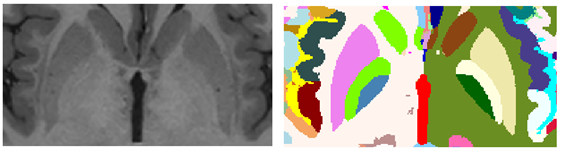

Pallidum integration

Finally, we decided to manually segment one structure for deep grey matter completeness. We divided the globus pallidum into its internal and external parts manually. This was done using ITK-SNAP from the entire pallidum segmentation obtained with vol2Brain pipeline. Figure 9 shows and example of the pallidum parcellation. This was done by JVM under the supervision of FA and MG.

Refer to caption

Figure 9: Left: T1w image. Right: Pallidum segmentation of their internal and external parts.